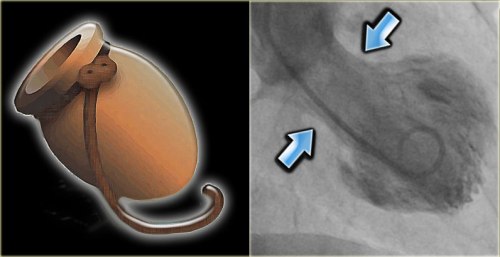

A 25 year man ,  hotel  manager  who had a documented DVT , since 2011 was on tablet warfarin . He discontinued  the drug by sheer miscommunication as he was told he should stop the  drug  beyond INR 3 by his general practitioner.He stopped it permanently  instead of titrating the dose of warfain .Six months later he landed  in August 2013 with an episode of minor hemoptysis . Clincally he was normal .His lower limbs were fine.

He was investigated and  his image file showed .

pulmonary embolism  3  total occlusion of LPA

pulmonary embolism total occlusion of LPA

Living with one lung

• He is comfortable with one lung function (Akin to  Pneumonectomy )

• His saturation was 100 % at room air

• Pulse -80/mt .BP 110/80mmhg

• His physical activity  did  not show any significant limitation (At worst class 2)

One of the cardiac surgery consultant wanted to do pulmonary embolectomy and endarteriectomy .

In fact , he was admitted in the critical care unit driven by the dramatic CT images.

One enthusiastic cardiologist wanted  thrombus aspiration and pig tail catheter based thrombolytic  irrigation within LPA !

How did we manage ?

• The risk of major vascular surgery was considered high in an absolutely asymptomatic individual .

• Intervention was considered too adventurous.

• He was  put on oral anticoagulant with target  INR 2.5-3.(After a 1 week Heparin overlap)

• We hope the thrombotic CTO will open up gradually but for surely .As the power of  natural lytic  molecules should not be underestimated as we have witnessed in LV and LA clot disappearing over months.

• However the option of putting IVC filter was strongly recommended for him , as he has only  functioning  lung  which  is threatened by a potential  embolus from DVT . The patient wanted to come back for IVC filter next month.

• He was also worked up for all those protein C, S,  Lieden mutation stuff.

• The patient was discharged in stable condition (By the way he  was never unstable either !)

* Meanwhile the hemoptysis  did not recur. CT scan showed a small wedge infarct in left lung that was in the healing mode.

Final message

This is a perfect example of  CTO of pulmonary artery being  managed conservatively* .We will let you know the follow up .